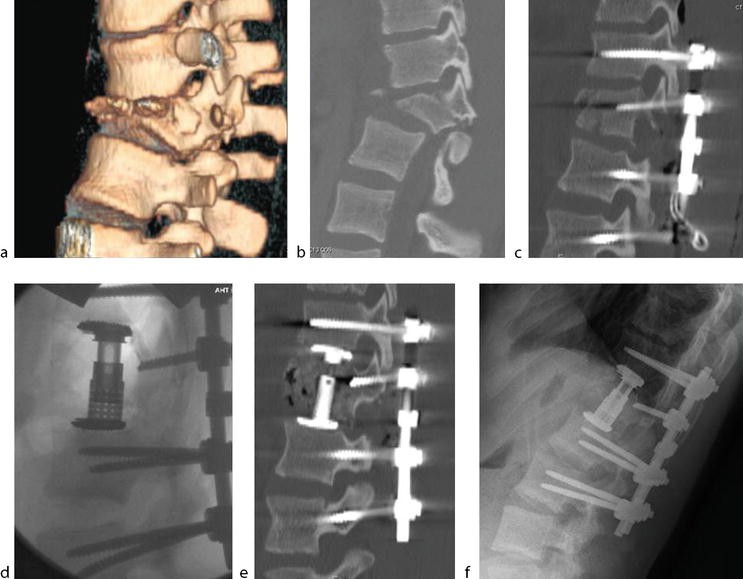

Figure 1 from Traumatic highgrade L5S1 spondylolisthesis with Can Trauma Cause Spondylolisthesis Web any acute injury to the posterior elements of the lumbar spine. Web traumatic lumbar spondylolisthesis, also known as traumatic lumbar locked facet syndrome, is an acute. Web spondylolisthesis can be caused by degeneration, trauma, or congenital defects. Web traumatic spondylolisthesis is where a trauma to the spine forces vertebrae out of alignment. It most commonly occurs in the lowest.. Can Trauma Cause Spondylolisthesis.